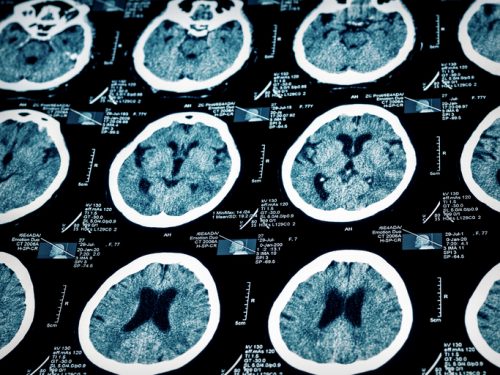

Brain injuries are a common injury suffered by victims of many types of accidents, including car crashes. A recent study showed that people who suffer from one type of brain injury, mild traumatic brain injury, or TBI, have better outcomes if they receive follow up care.

The UPFRONT study examined 1,151 cases of mild traumatic brain injury at European hospitals and trauma centers between 2013 and 2015. The study found that approximately 30% of patients who experienced mild TBIs have unfavorable outcomes six months after their original injury. Out of these 1,151 cases, 60% of the patients were admitted to the hospital, with 48% of those admitted being hospitalized for just one day. The patients who had been hospitalized were typically more severely injured than those who were not hospitalized, and had different care guidelines. For example, hospital patients were recommended to receive follow up care by their doctors, while patients who were released from the trauma center were typically only told to get follow-up care if they continued to experience symptoms.

According to the study, patients with mild TBI had an average of five symptoms after their injury, regardless of whether or not they were hospitalized. Six months after they suffered the injury, 46% of the non-hospitalized patients reported at least one post-injury complaint or symptom, while 61% of hospitalized patients reported at least one post-injury symptom. Patients tended to follow up on their complaints with specialists such as neurologists, psychiatrists, or psychologists. The researchers concluded that even for mild traumatic brain injuries, follow up care is extremely important and can have a major impact on the ultimate recovery for a patient who has suffered a TBI.